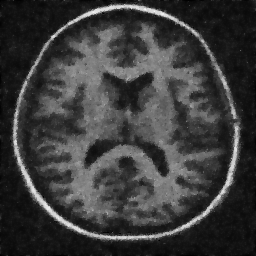

4.1. Uniform Gaussian noise

In this first experiment, we consider the denoising problem with brain scan images. The first set consists of images of pixels and Gaussian noise with zero mean and variance . The original and noisy images are shown in Figure 4.1. The domain decomposition-semismooth Newton algorithms run with the parameter values , , and . The results are shown in Figure 4.2. From the surface representation of , we can observe that is continuous and its shape is related to the one of the original image. In particular, the regularization is stronger in homogeneous regions in the image, and weaker where the image intensity undergoes variations on a smaller scale.

In Table 4.1 the performance of the different methods is compared. For all of them, only the first 2 domain decomposition iterations were considered. The total number of SSN iterations differ at most by one. The impact of the domain decomposition method becomes clear when comparing the computing times of the methods, corresponding to one, two and four subdomains. The computing time is significantly reduced. The effect of the optimized transmission conditions can be realized when comparing the gap between subdomains, which is much lower in the case of optimized transmission conditions () than in the standard Schwarz method ().